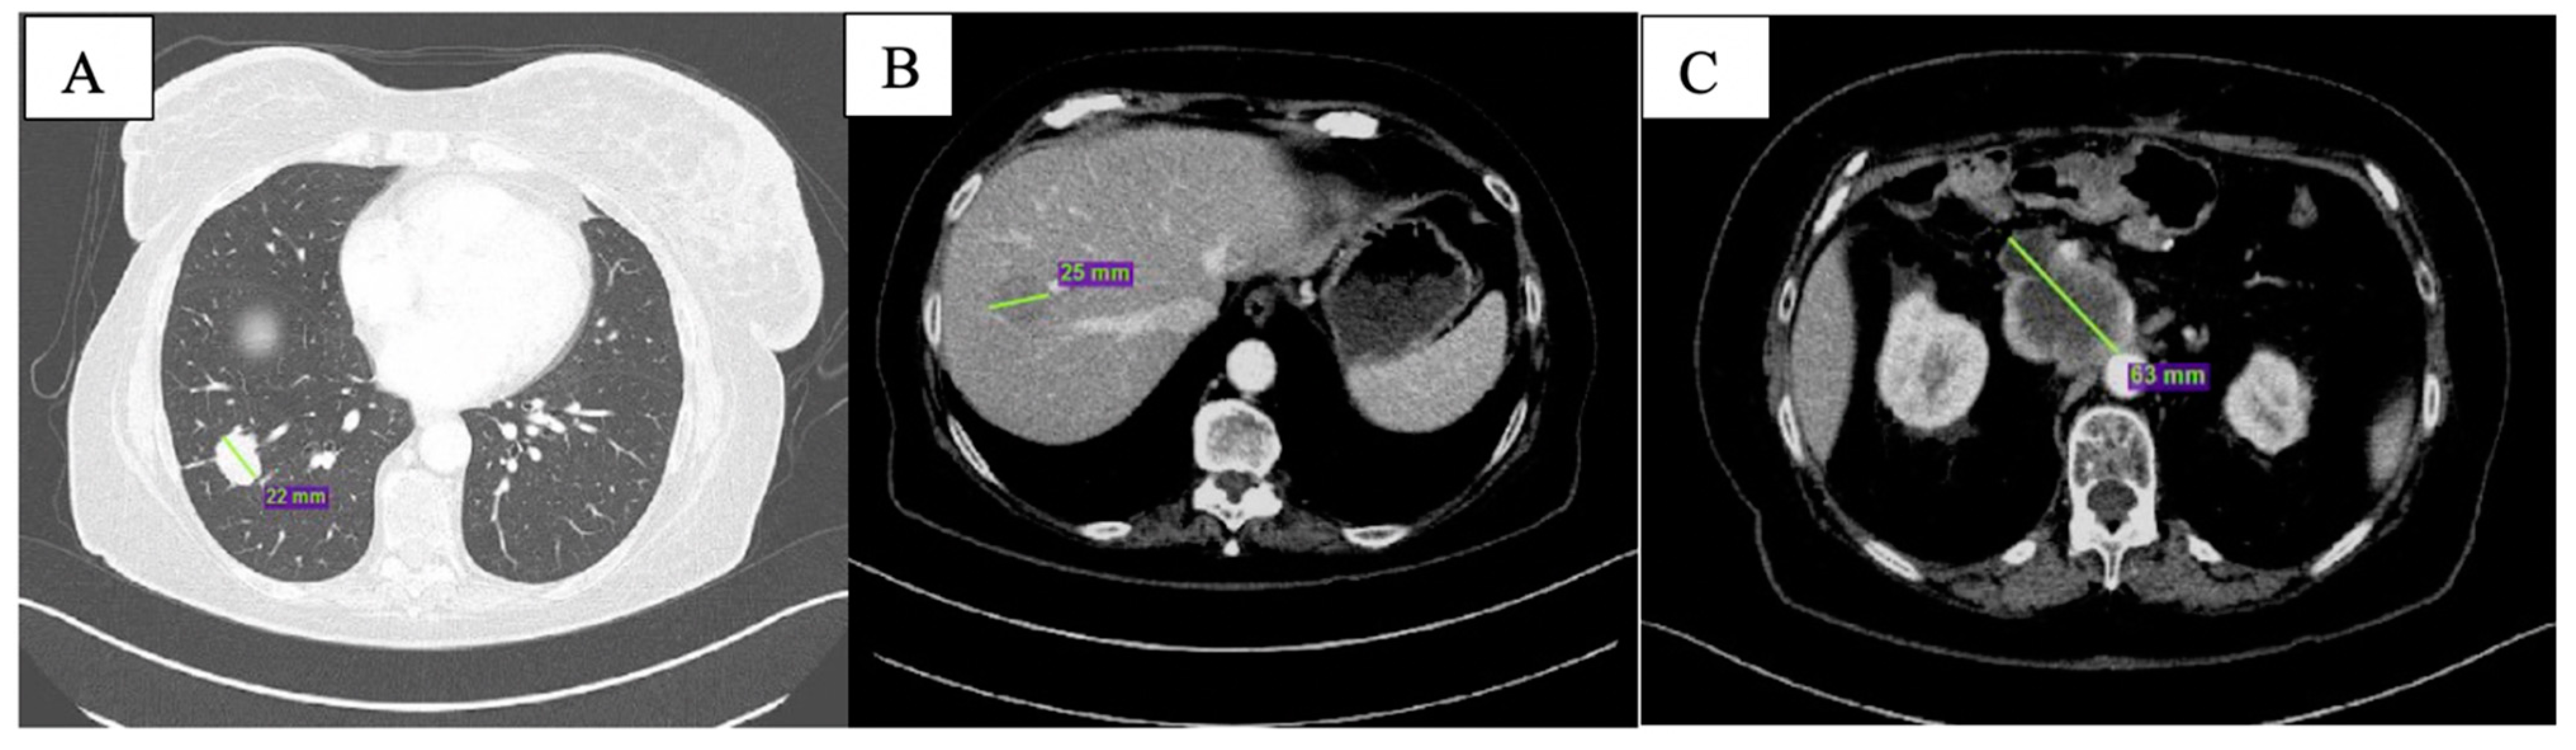

At CT scan in January 2019, both pulmonary and nodal lesions were augmented in volume; new hepatic lesions were also documented (Figure 1).

Figure 1.

Baseline CT scan showing nodular lesion in inferior lobe of the right lung (A), hepatic lesion in the 8th segment (B) and peripancreatic tissue (C).